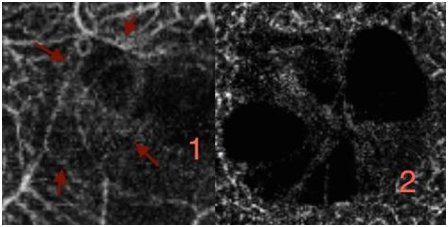

No abnormal «flow» signal is present, normal vessels are well individualized; choriocapillaris lobules are shown like clusters of half light signal. For now the best images we can obtain are 3X3 mm, possibly 6X6 mm and as a result of which the main use is centered on macula, and on ARMD In this case of subretinal new vessel which is a minimally classic choroidal new vessel7 (Figure 2) you can clearly see an abnormal flow signal pointed in red, followed by the OCT, confirmed by AF In one shot you diagnose a choroidal neovascularization and you replace AF and indocyanine green angiography (ICG). Angio OCT is also very contributive for retinal angiomatous proliferation (RAP), you can analyze your different layer and determine the course of the rap and nearly the complete morphology of the lesion. The analysis of the RAP could begin from the internal retina to the choroid In rap you observe at the retinal level, a deviation and dilation of retinal vessels in outer and medial retina (Figure 3) then you reach the anastomosis (Figure 4(1)) and the shape of the angiomatous lesion and nearly the total morphology of it (Figure 4(2,3)), the images are really better and more didactic than ICG and FA (Figure 5(1−3). The follow up of new vessels is also very interesting, with the confrontation of OCT you can easily highlight the activity of the new vessels (anastomosis, reflectance) and the regression of this activity after treatment (Figure 5−8) with sometimes very impressive images of «resting» new vessels (Figure 8,9) Angio OCT is also helpful to affirm the non vascular activity of a pigment epithelium detachment (Figure 10).

Figure 3 RAP (1) outer retina (2) media retina.

Figure 4 The discovery of the RAP, three different layers to show the shape of the RAP.

Figure 5 Three different approach of the rap. (1) Angio OCT. (2) FA. (3) ICG (red arrow on the RAP the scales of the images are different between Angio OCT and FA /ICG The evolution before (4) and after intravitreal ranibizumab (5).